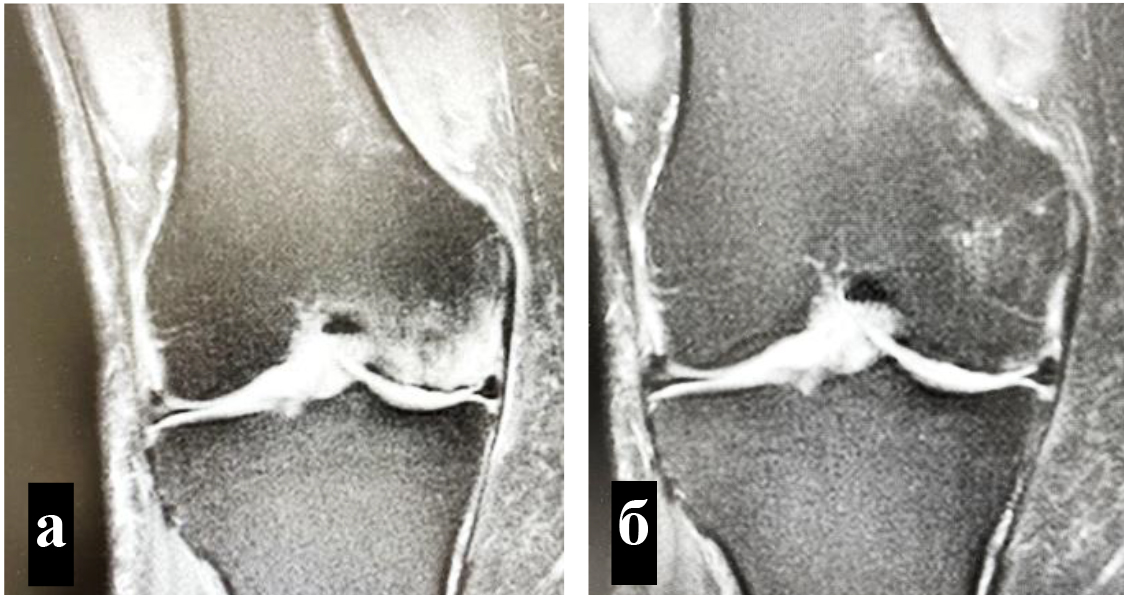

Техника подготовки препарата и инъекции. Забор крови и приготовление ОТП выполняли в условиях процедурного кабинета или перевязочной при соблюдении необходимых правил асептики и антисептики. Согласно методике YCELLBIO PRP (Корея), двухкратно центрифугировали кровь пациента и получали 3 мл ОТП, которую центрировали в узком перешейке пробирки и забирали при помощи шприца (рис. 2) Количество тромбоцитов в готовом препарате составляло 962 ± 40 × 109/л.

Рис. 2. Этапы приготовления ОТП: а – центрирование лейкотромбоцитарного стоя в перешейке пробирки YCELLBIO; б – забор лейкотромбоцитарного слоя при помощи шприца